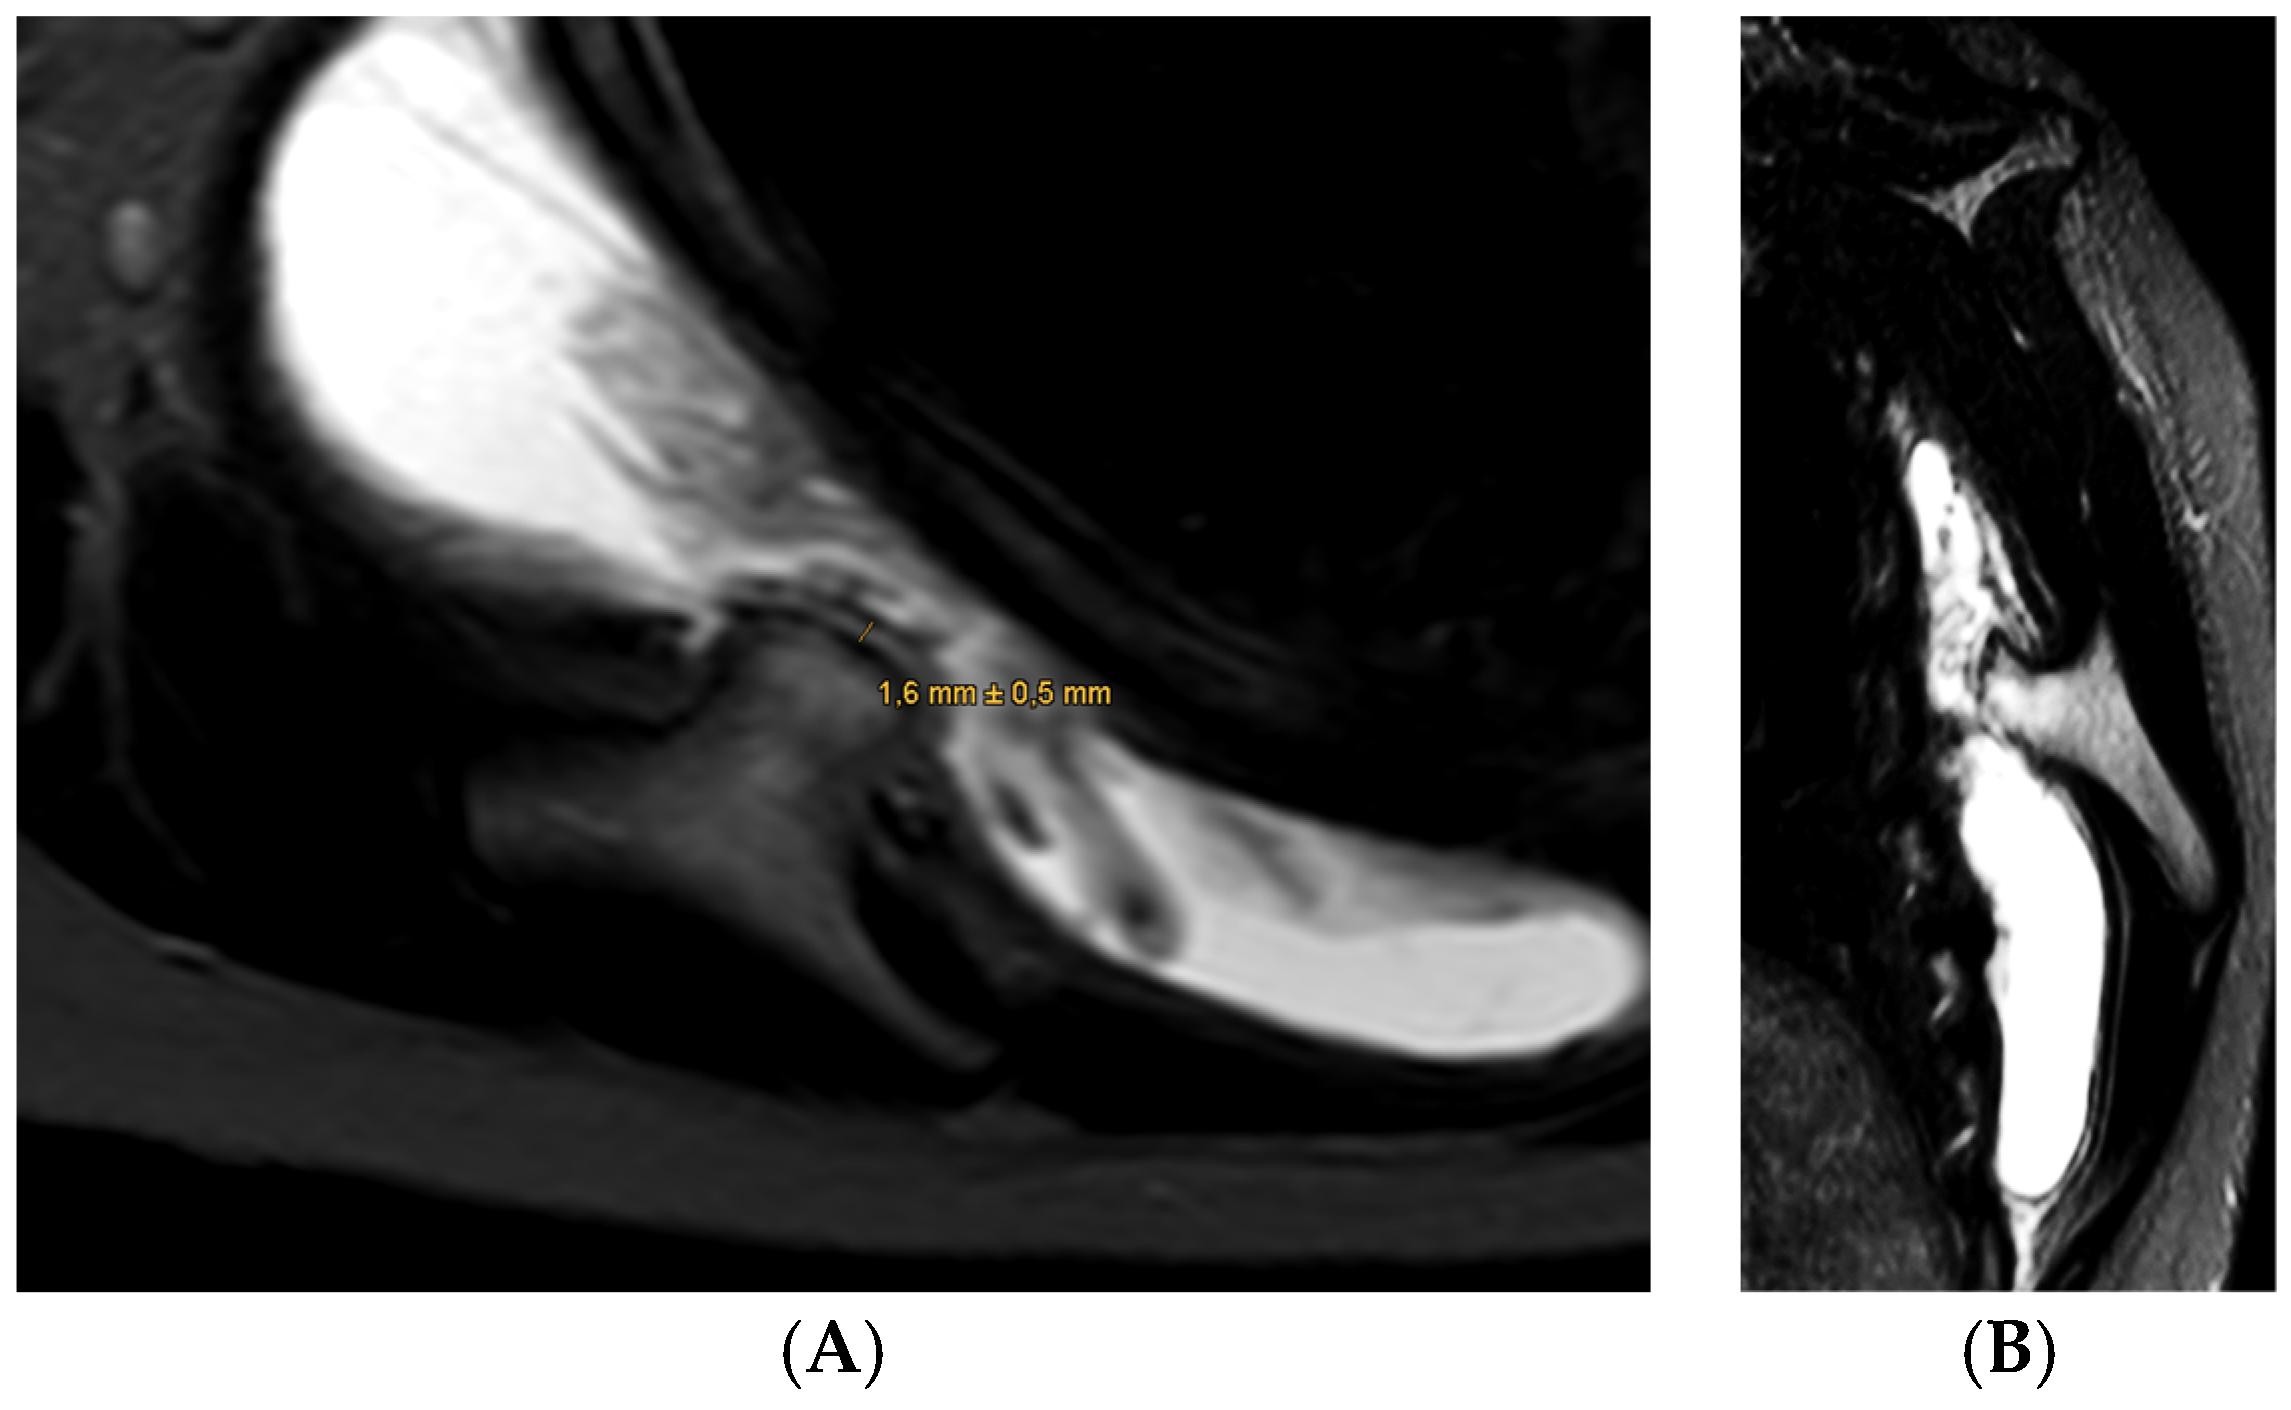

- Visualization: The arthroscope is introduced through the posterior portal. Initial visualization targets the inflamed scapulothoracic bursa to gain orientation (Figure 3A,B). In the present case, the exostosis was partially protruding through the subscapularis muscle and thus visible upon entry. A blunt dissection plane is established between the scapula and the subscapularis muscle to expose the exostosis base.